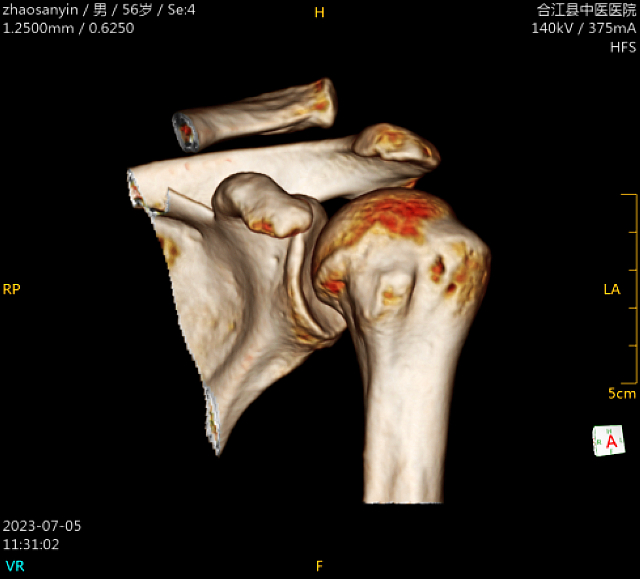

该患者因外伤致左肩部疼痛、活动受限,左肩锁关节压痛明显,肩关节活动受限,琴键征(+)。入院后检查提示,左肩锁关节脱位(RockwoodⅢ型)。

术前影像

术中C臂透视